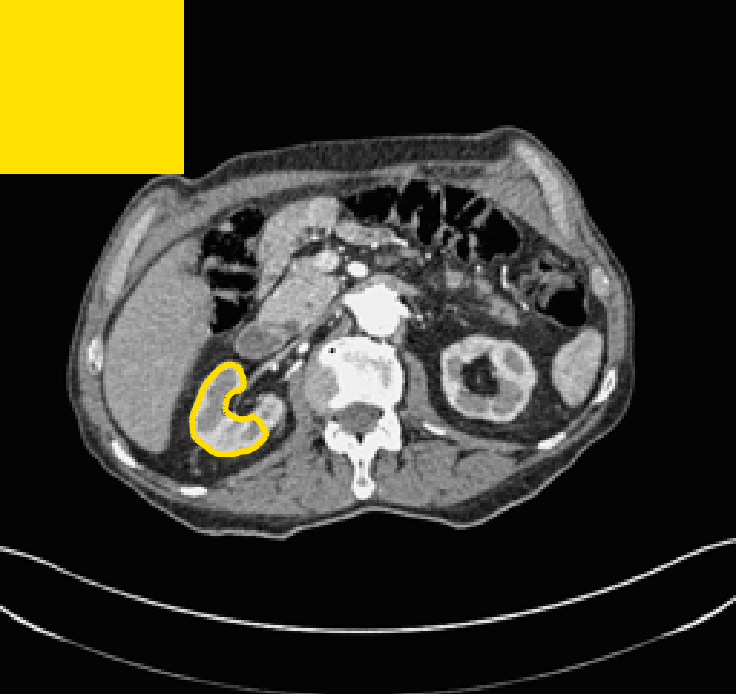

The motivation for this work comes from observing contradictions in using piecewise-constant intensity fitting terms in selective segmentation. Whilst good results are possible with this approach, the exceptional cases lead to severe limitations in practice. This is quite common in medical imaging as demonstrated in Fig. 1, where the target foreground has a low intensity. Given that the corresponding background includes large regions of low intensity, the optimal average intensities for this segmentation problem are and . For cases where , we see that by (1), almost everywhere in the domain . This means that it is very difficult to achieve an adequate result, without an over-reliance on the user input or parameter selection.

for and as defined in (33). This is consistent with respect to the intensities of the observed object and the concept of selective segmentation. In Fig. 3 we see the difference between CV and the proposed fitting terms for given user input on a CT image. For the CT image, the CV fitting terms are near 0 within the target region. This is despite there being a distinct homogeneous area with good contrast on the boundary. This illustrates the problem we are aiming to overcome. With the proposed fitting term this phenomenon should be avoided in cases like this. By defining as in (33) there is no contradiction if the foreground and background intensities of the target region are similar.

The TC values for the parameter sets are presented as heatmaps in Figs. 11–13. A heatmap is a convenient way to display accuracy results for hundreds of tests concisely. In Fig. 9 we give an example heatmap with the same axes used for those in Figs. 11–13. For each of the combinations of parameter values we give the TC value of the segmentation result and represent it by the appropriate colour. The corresponding colour scale is shown in Fig. 8. Qualitatively, the more green areas of the heatmap the more accurate the model is for a wider set of parameters. Example results for Test Image 5 when varying (with ) for the proposed model are given in Fig. 10. Here it can be seen what each accuracy result corresponds to visually.